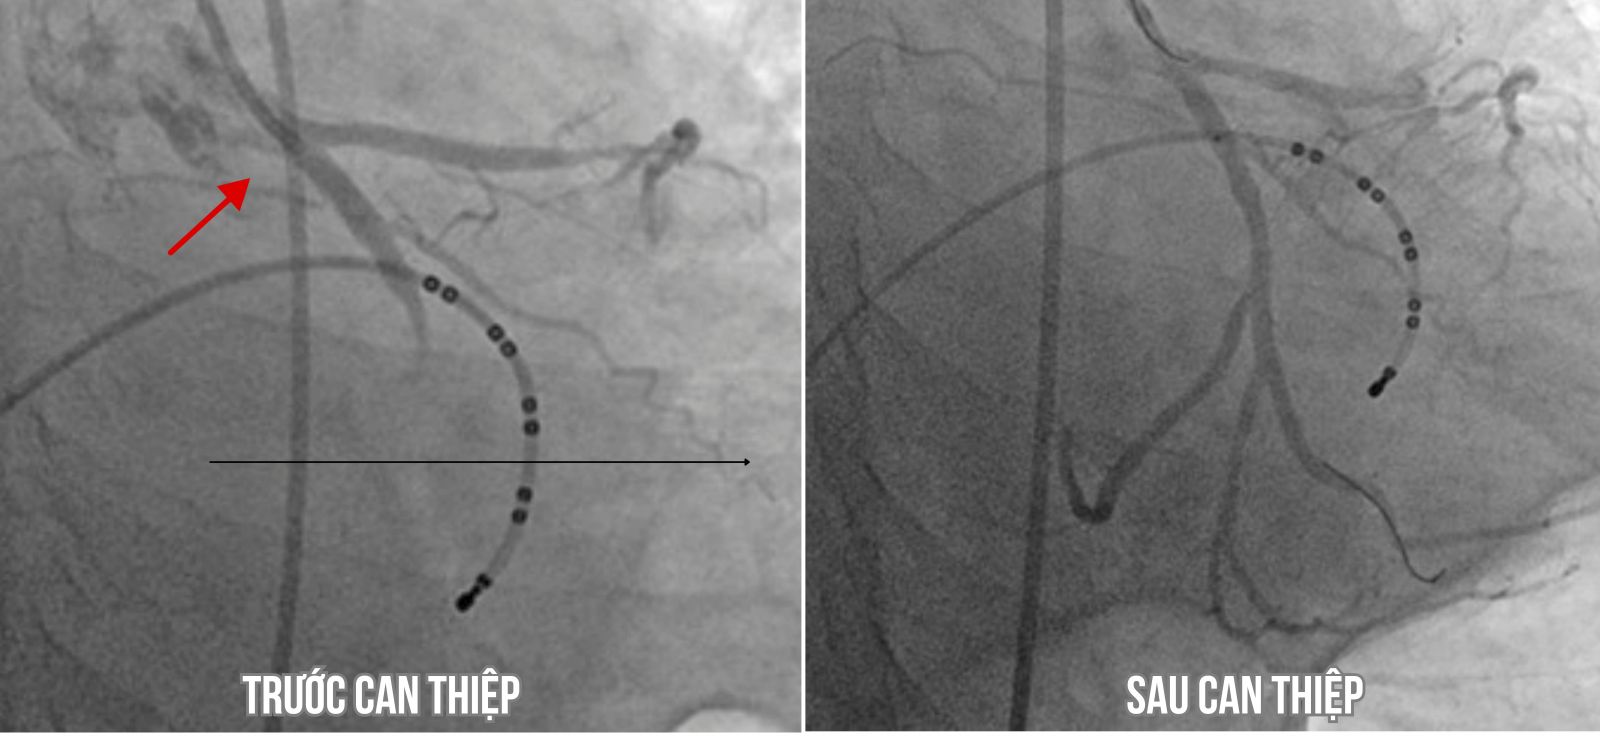

Hình ảnh mạch vành người bệnh tắc hoàn toàn động mạch mũ và sau khi can thiệp đặt stent tại vị trí mạch vành bị tắc.

Được sự hỗ trợ của các khoa Cấp cứu, Hồi sức tích cực - chống độc, Gây mê hồi sức và Nội tim mạch, bệnh nhân nhanh chóng được ổn định huyết áp, dùng thuốc điều trị rối loạn nhịp và được chuyển đến phòng DSA để đặt máy tạo nhịp tạm thời và chụp mạch vành cấp cứu. Kết quả chụp mạch vành cho thấy tắc hoàn toàn động mạch mũ, hẹp 90% động mạch liên thất trước. Tổn thương mạch vành thủ phạm được hút huyết khối, nong bóng và được đặt stent tại vị trí mạch vành bị tắc.